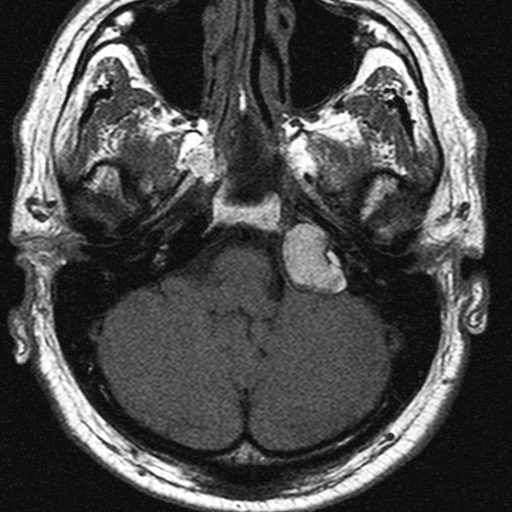

1. image: Patient with sensorineural hearing loss and tinnitus. MR-study (T2, precontrast T1 and postcontrast T1) reveal a mass in the left pontocerebellar angle without significant contrast enhancement. HRCT proves that the mass arises from the petrous pyramid, suggesting cholesterol granuloma. (Asklepios Klinik Altona, Hamburg)